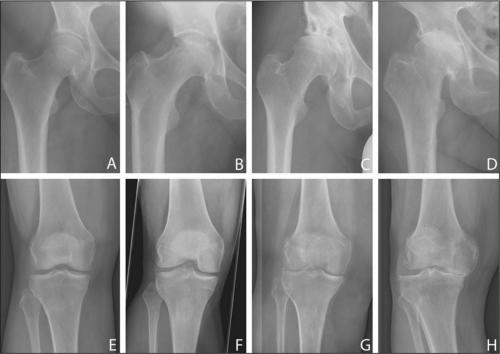

Слева — направо ухудшение состояния сустава при артрозе.

Некоторые люди задают вопрос: поможет ли диета при артрозе голеностопного или тазобедренного сустава? Давайте с самого начала уясним: остеоартроз – это системное заболевание. Следовательно, принципы питания при нем одинаковы (независимо от того, какой сустав пострадал).